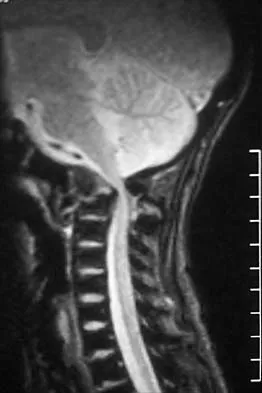

A 14-year-old girl with polyarticular juvenile rheumatoid arthritis (JRA) has severe neck pain and reports the onset of urinary incontinence. A lateral radiograph and lateral tomogram of the cervical spine are shown in Figures 15a and 15b. An MRI scan of the upper cervical spine is shown in Figure 15c. Management should consist of

Explanation